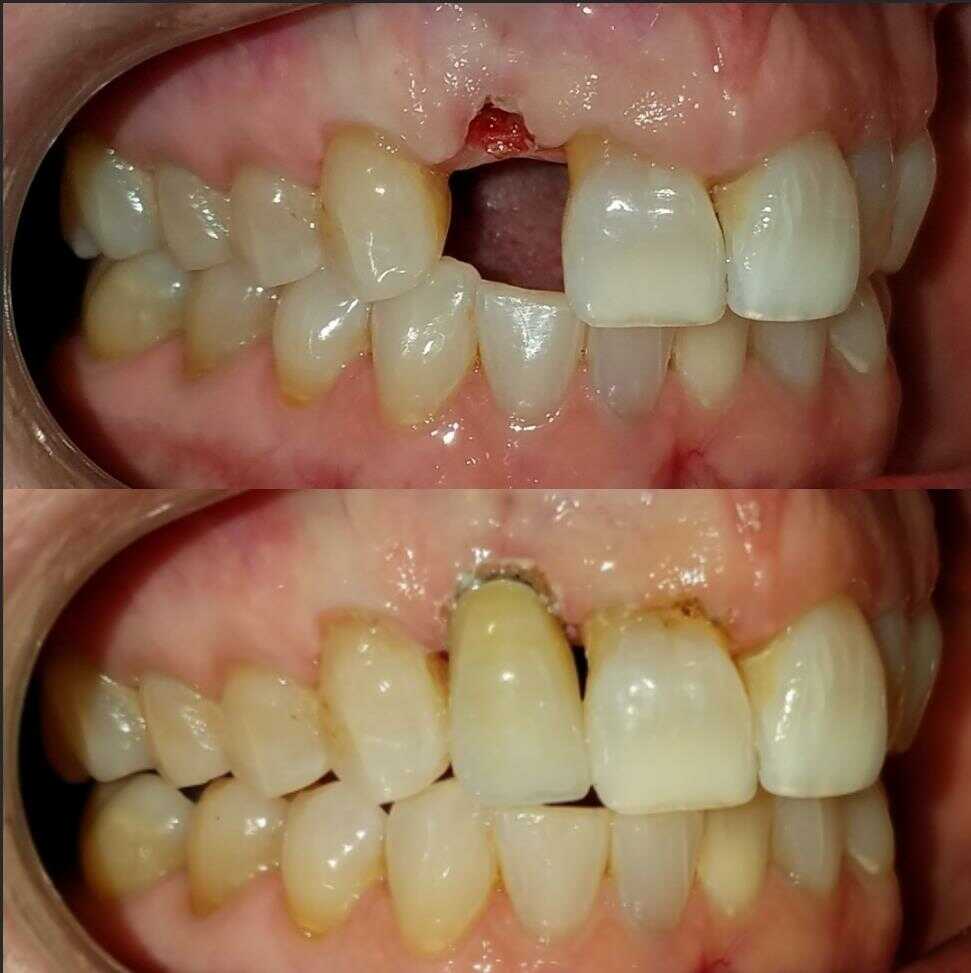

VENEERS & CROWNS: before and after

DENTAL IMPLANTS: before and after